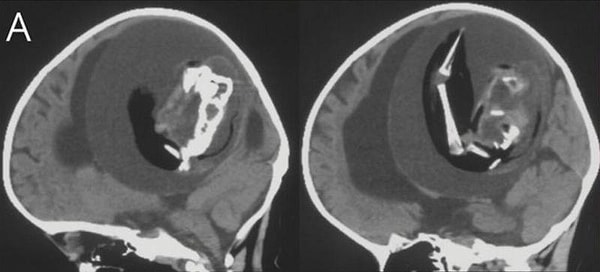

Как только МРТ показала существование близнеца, который давил на ее мозг, врачи поняли, что плод нужно немедленно удалить. К тому времени, как они смогли извлечь его, близнец уже несколько месяцев рос внутри черепа малышки — у него развились кости, органы и конечности.

Этот случай был тщательно изучен и опубликован в виде истории в журнале Neurology.

Доктор Цзунцзе Ли, невролог из больницы Хуашань, который лечил девочку, рассказал: «Предполагается, что внутричерепной плод-в-плоде возникает из неразделенных бластоцист. Соединенные части развиваются в передний мозг плода-хозяина и обволакивают другой эмбрион во время роста нервной пластинки».